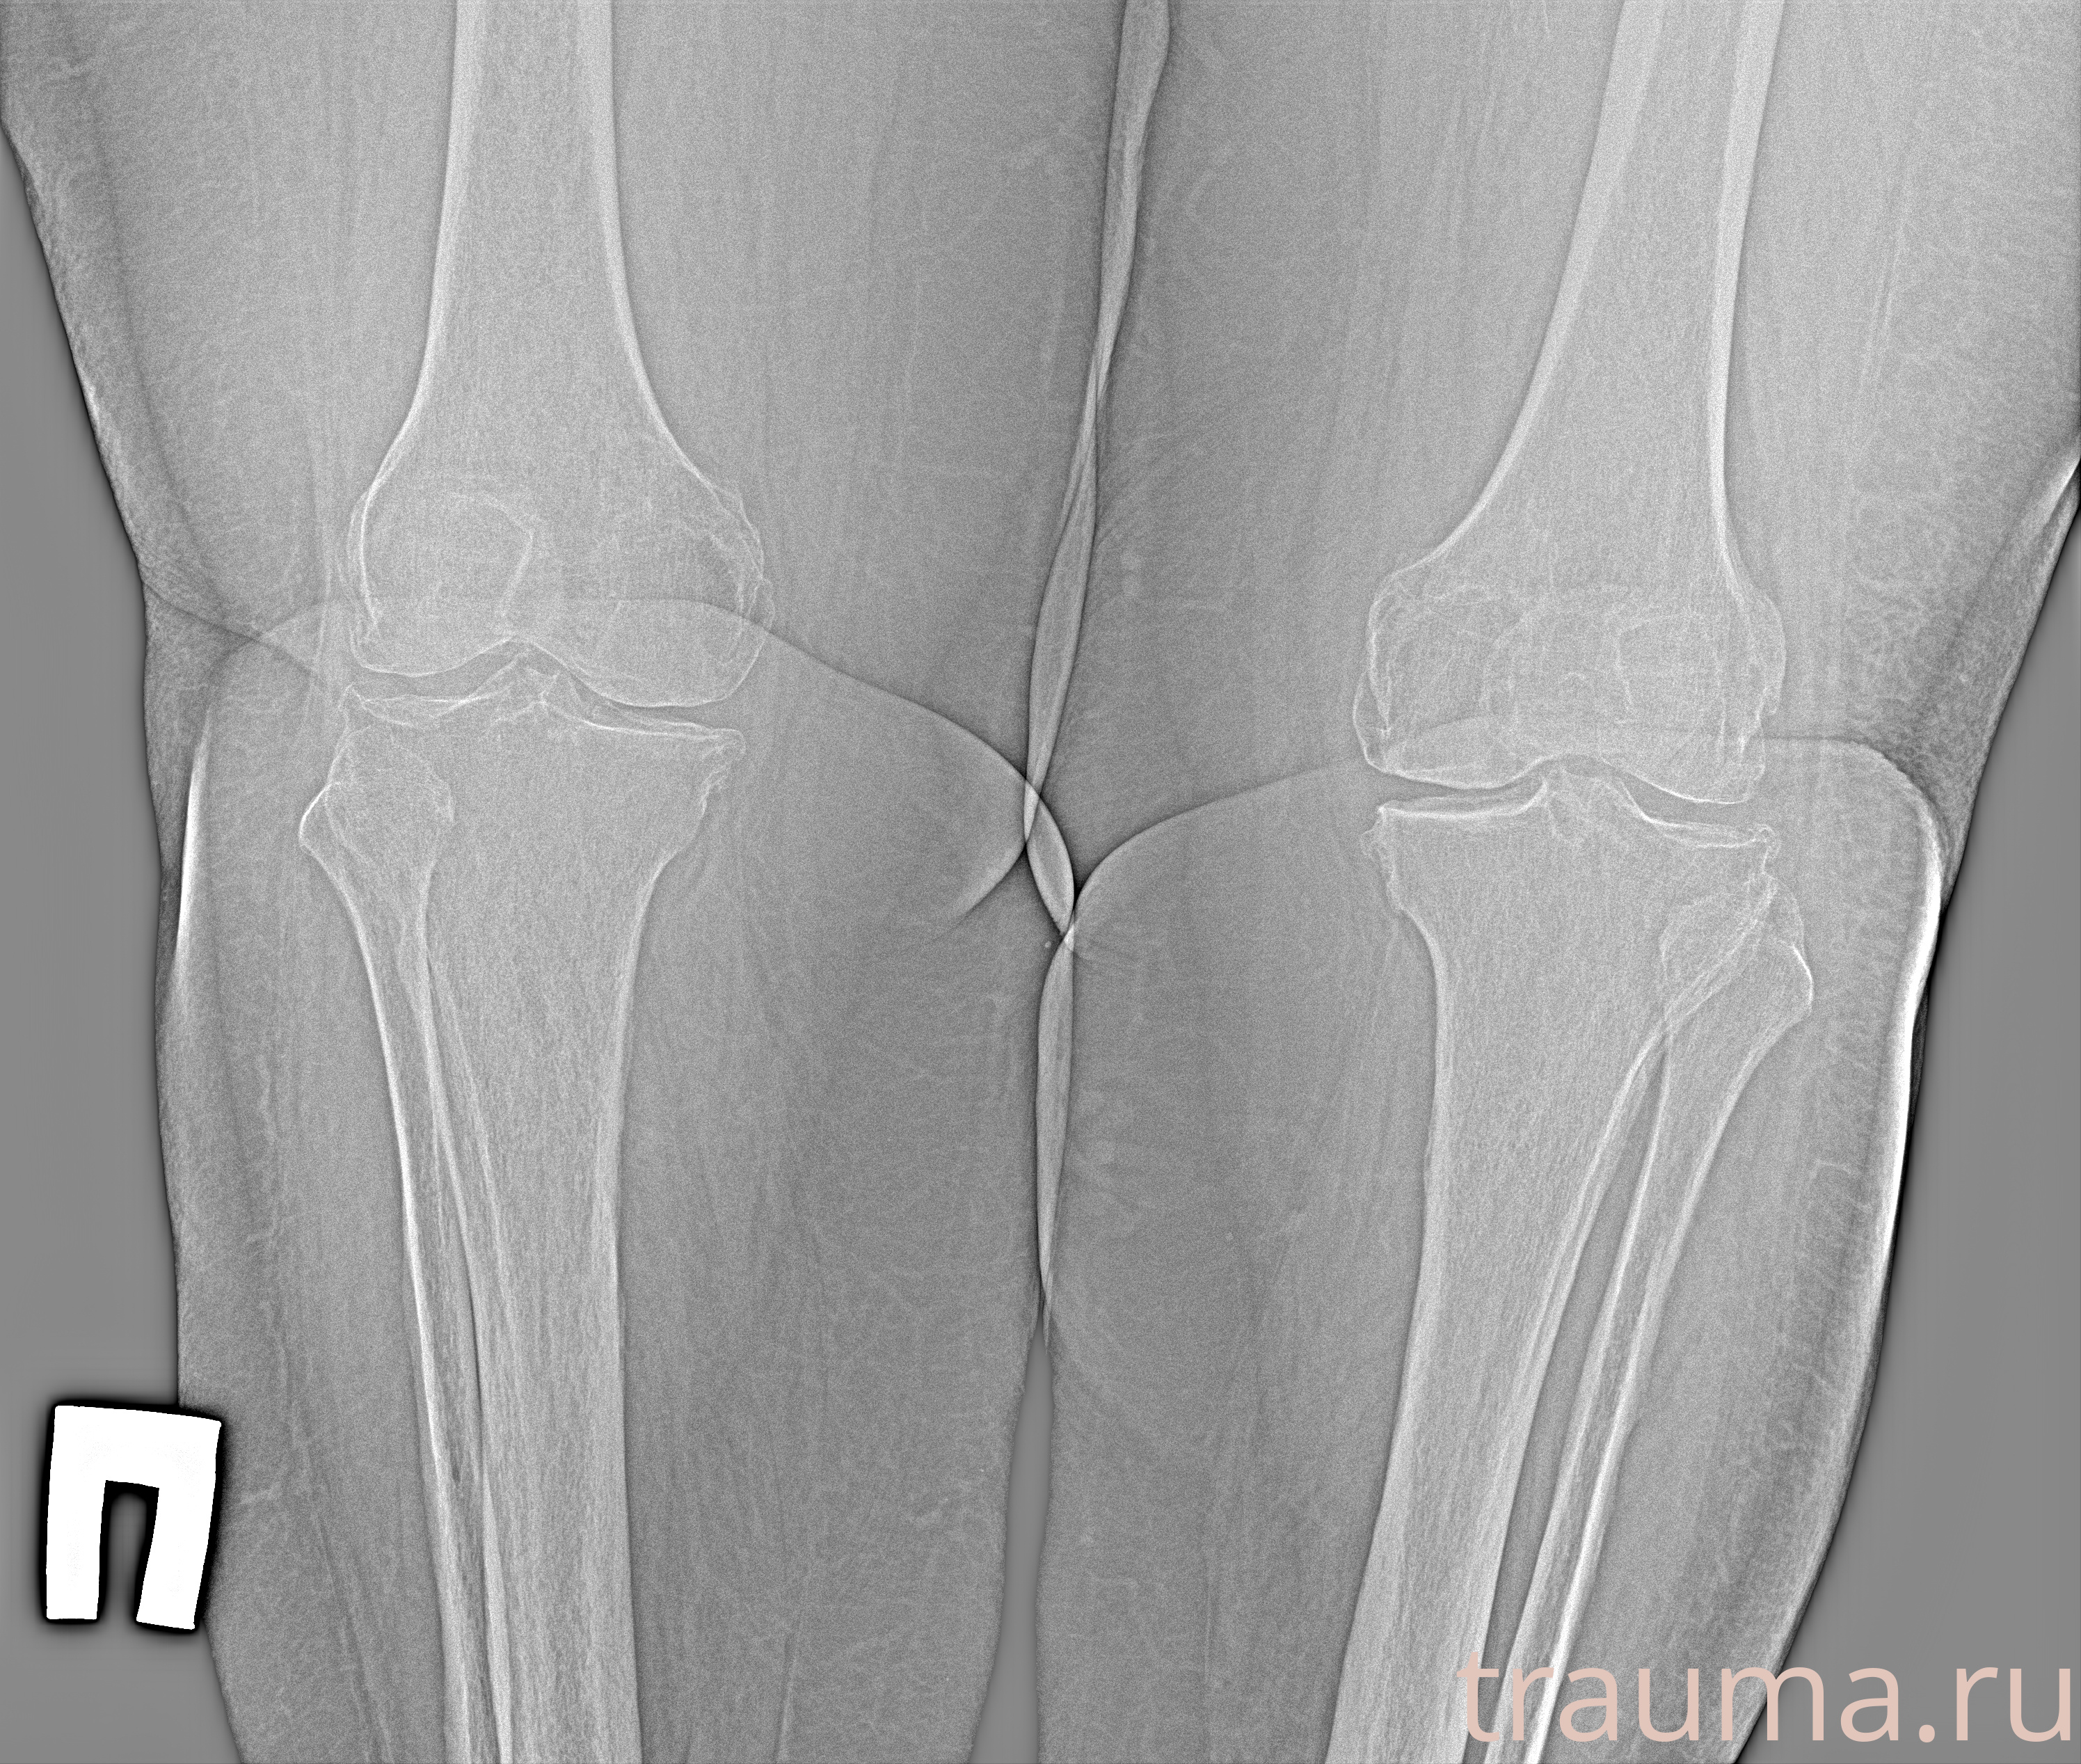

Рентген на дому: по вашему адресу приезжает врач-рентгенолог, травматолог-ортопед с мобильным рентгеновским аппаратом, проводит диагностику травмы или заболевания, делает необходимые рентгенограммы, дает рекомендации по дальнейшему лечению. Получить качественные снимки в домашних условиях возможно благодаря уникальной методике, разработанной МосРентген Центром для института  Склифосовского